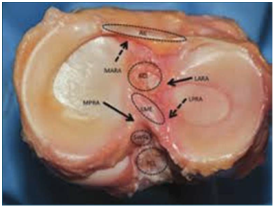

半月板损伤也可以由膝关节退变造成。在严重创伤病例,半月板,十字韧带和侧副韧带可同时损伤。半月板损伤的部位可发生在半月板的前角、后角、中部或边缘部。损伤的形状可为横裂、纵裂、水平裂或不规则形,甚至破碎成关节内游离体。

正常的半月板